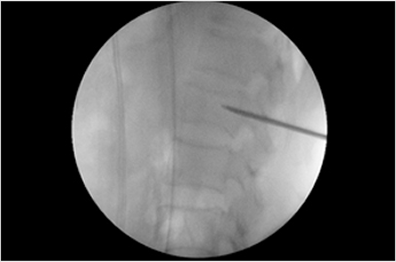

간단한 국소 마취 후 X-선 투시기를 이용하여 압박된 척추 뼈를 실시간으로 확인하면서, 특수한 주사기를 통해 ‘골 시멘트’라 불리는 강화제를 주입하여 척추 뼈를 단단하게 복원하고 높이를 유지시킵니다.

척추성형술 환자 시술 사례

척추성형술 환자 시술 사례 척추성형술 환자 시술 사례